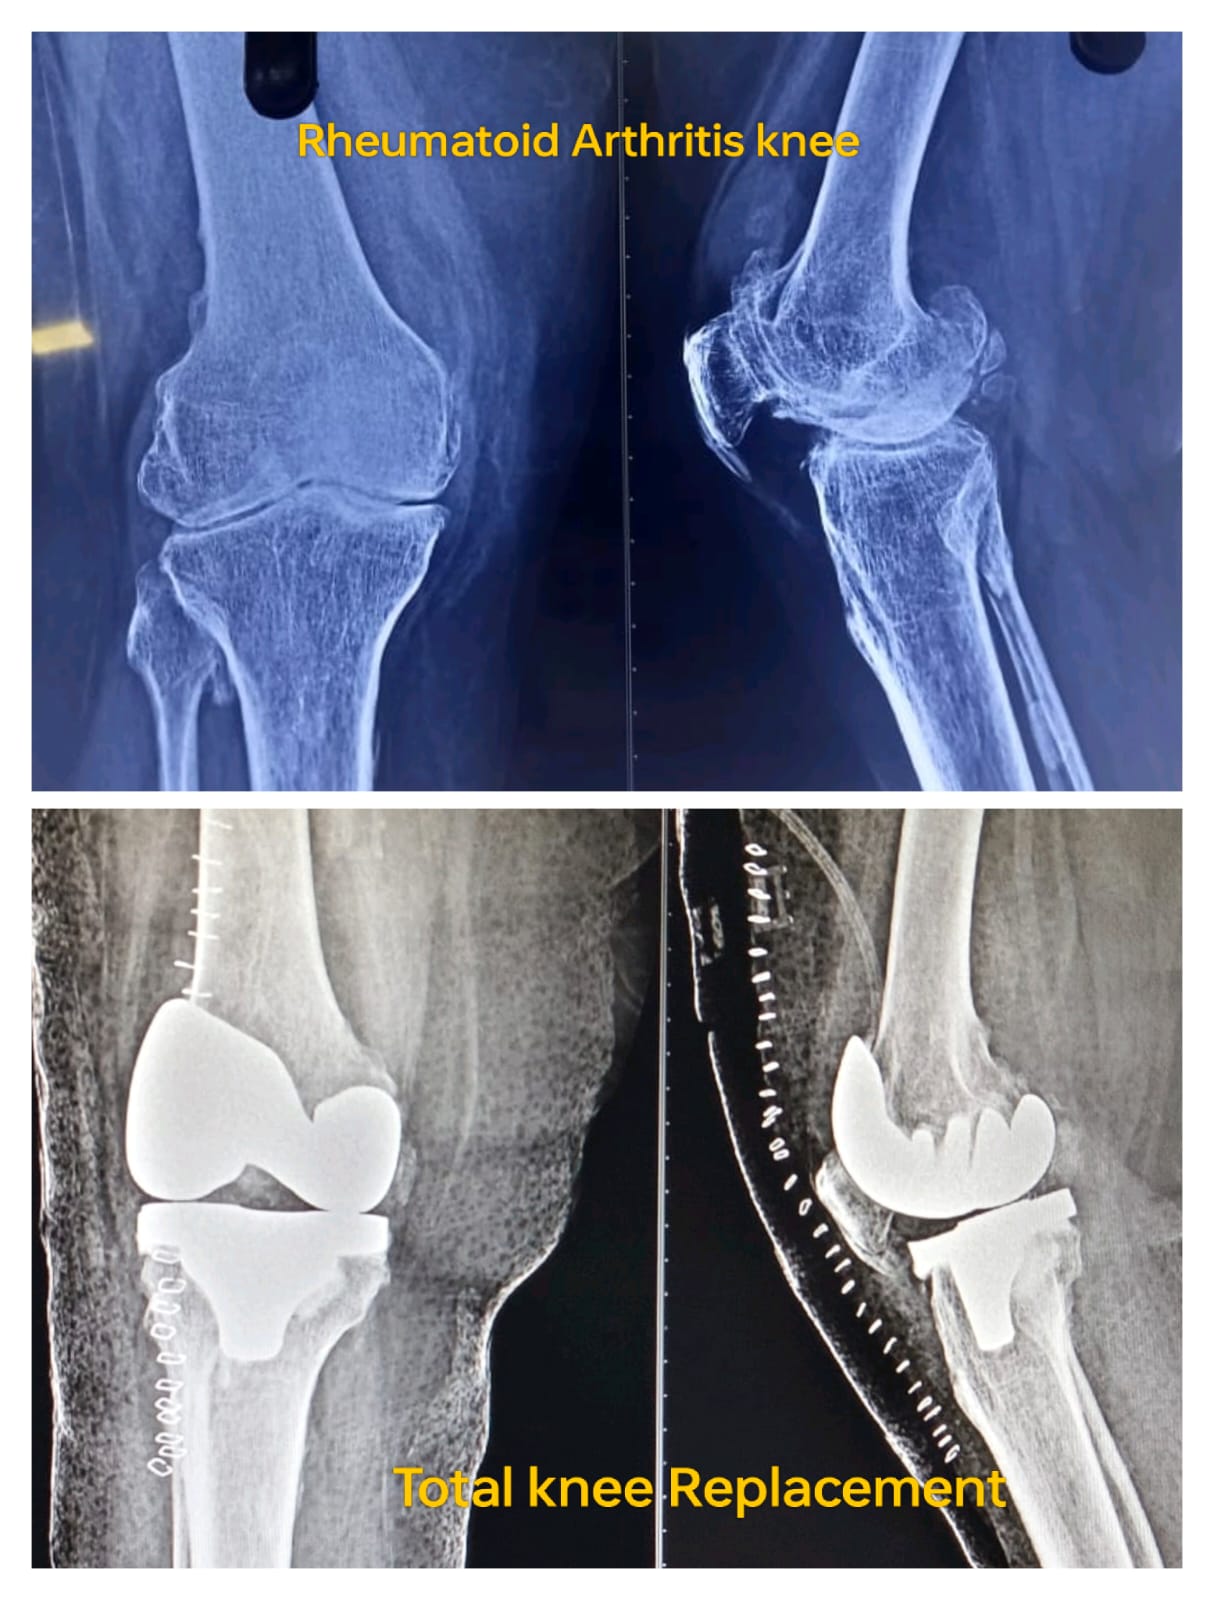

Knee Arthroplasty is a surgical procedure where I replace a damaged knee joint with an artificial implant to restore function and relieve pain. This procedure is most suitable for patients with severe osteoarthritis, rheumatoid arthritis, post-traumatic arthritis, or cartilage damage that limits mobility. By replacing only the affected parts (partial knee replacement) or the entire joint (total knee replacement), I can tailor the surgery to each patient’s condition.

During knee replacement surgery, I remove the damaged cartilage and bone from the knee joint and replace it with a durable artificial implant. I use precise surgical techniques to ensure accurate alignment, stability, and joint function. Depending on the patient’s needs, I may perform total knee replacement or partial knee replacement. Each procedure is carefully planned and executed to maximize outcomes and minimize recovery time.

Preparation for Knee Replacement

• Imaging Tests: X-rays, MRI for surgical planning